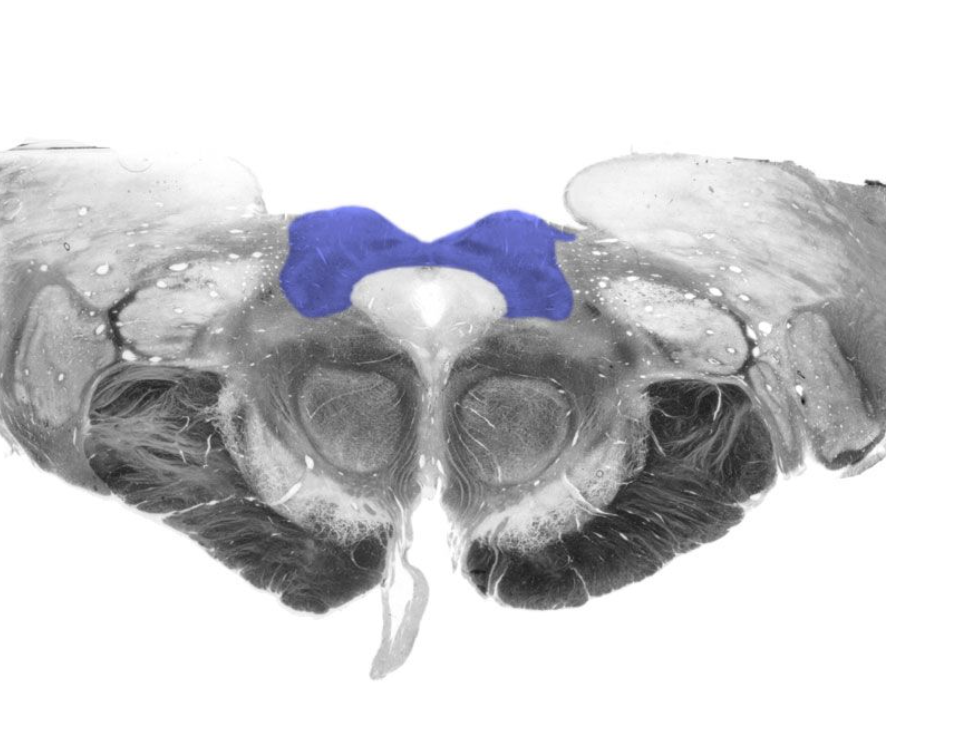

Dorsal column nuclei

Gracile nucleus and cuneate nucleus; contain the second-order sensory neurons that relay mechanosensory information from peripheral receptors in the body (excluding the face) to the thalamus via the medial lemniscus. The dorsal column nuclei are located in the lower medulla.

Nucleus gracilis

Nucleus containing the second-order sensory neurons that relay mechanosensory information from peripheral receptors in the lower body to the thalamus via the medial lemniscus, located in the lower medulla (also called the "gracile nucleus"). The nucleus gracilis also relays visceral pain information from second-order neurons in the central spinal cord to the thalamus.

Nucleus cuneatus

Dorsal column nucleus in the lower medulla; contains second-order sensory neurons that relay mechanosensory information from peripheral receptors in the upper extremities to the thalamus via the medial lemniscus.